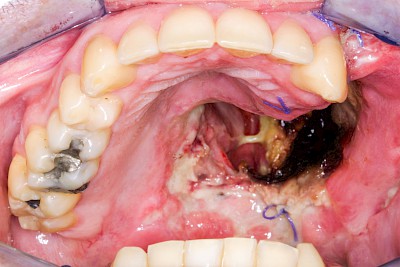

Einschmelzung & Geschwür

Das Risiko für Krebs der Mundhöhlen-Schleimhäute ist bei Menschen, die jahrelang übermäßig viel (Abusus) geraucht und erst recht lange übermäßig viel Alkohol getrunken haben, stark erhöht. Die Schleimhäute sehen dann aus wie "wildes Fleisch" – entweder mit blumenkohlartigen Auftreibungen oder aber es zeigen sich großflächige ungleichmäßig geformte Defekte und Einschmelzungen. Man spricht dann auch von einem Geschwür (Ulcus).

Entsteht der Krebs eher in tieferliegenden Schichten (z. B. im Bereich der Speicheldrüsen), sind die Auffälligkeiten nicht so deutlich. Hier fallen eher Seitenunterschiede links und rechts im Bereich der Mundhöhle auf. Auch plötzlich auftretendes und wiederholtes Nasenbluten, Einschränkungen der Atmung durch die Nase können Anzeichen für einen Tumor im Bereich der Nasen- oder Kieferhöhle sein.

Selten können auch Fibrome oder Druckstellen bei Zahnprothesen, wenn diese nicht erkannt und behandelt werden, in "wildes Fleisch" übergehen und hin zu bösartigen Tumoren entarten.

Bei allen diesen Auffälligkeiten ist eine sofortige (zahn-)ärztliche Abklärung zu veranlassen.